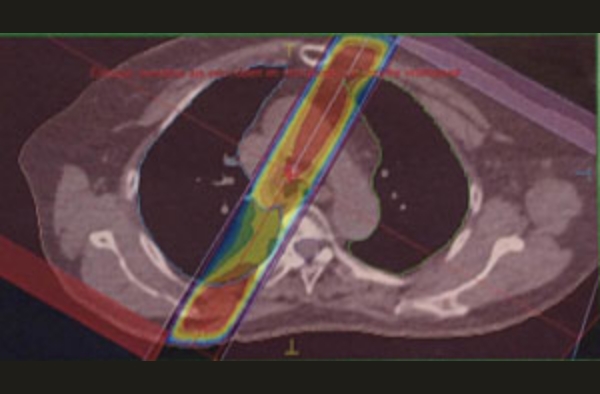

小肺がんの照射

肺がん+リンパ節

はじめのうちは、広く照射。その後、縮小照射正常肺にできるだけ当たらないように3個に分けて照射